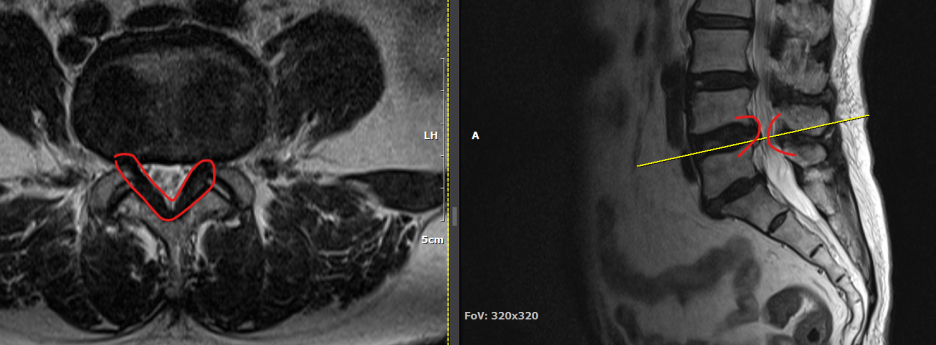

척추관 협착증은 척추관이 좁아지거나 협착되어 척수나 신경근을 압박하는 상태를 말합니다. 이런 경우, 양방향 척추 내시경이 매우 유용한 치료 수단이 될 수 있습니다.

- 계획: 양방향 척추 내시경은 미세한 카메라와 도구를 사용하여 척수와 주변 신경 구조를 정밀하게 시각화할 수 있습니다. 이를 통해 정확한 진단을 내릴 수 있으며, 각 환자에게 맞는 개별적인 수술 계획을 수립할 수 있습니다.